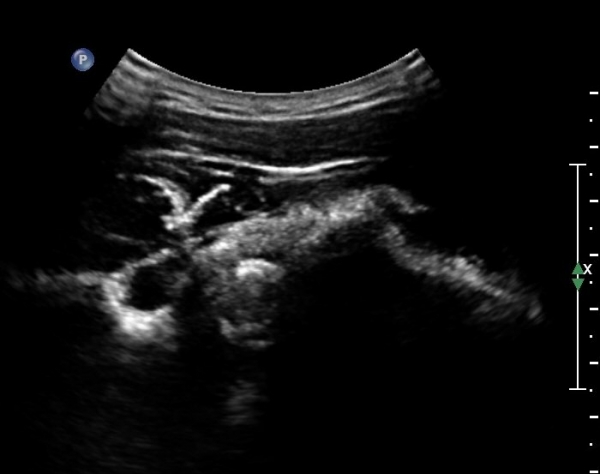

ÄÁº¤½ºÅ½ÃËÀÚ¸¦ ÀÌ¿ëÇÑ ¾î±ú µÚÂÊ È¾´Ü¸é°Ë»ç¿¡¼­ °üÀý¿Í ³»Ãø ¼ö¾× Àú·ù¿Í °üÀý¿Í¼ø ÆÄ¿­ÀÌ

°üÂûµÈ´Ù(»çÁø 3, 4, 5, 6).